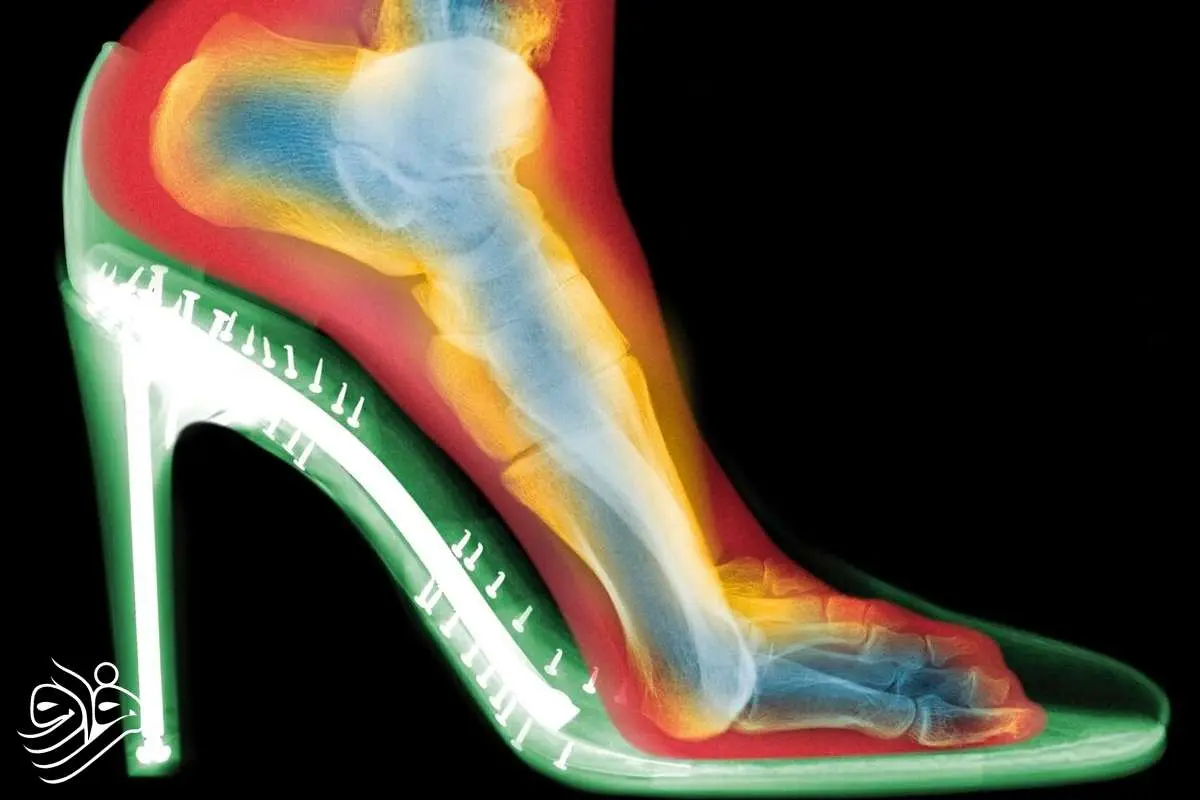

اسکن‌های سه‌بعدی چه نشان دادند؟

گلدبرگ دو اسکن از پای یک فرد تهیه کرد: یکی بدون کفش و دیگری با کفش پاشنه‌بلند. تفاوت‌ها چشمگیر بود:

فشردگی انگشتان :  انگشتان پا در کفش به هم فشرده شده بودند؛

انحراف شست پا (بونیون) :  مفصل انگشت شست به طرف بیرون متمایل شده بود؛

انگشتان چنگالی :  انگشتان کوچک‌تر برای حفظ تعادل، حالتی قفل‌شده و خمیده به خود گرفته بودند.